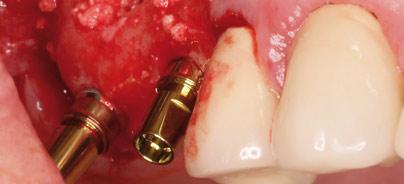

Emergenzprofil und Implantatposition

Pfeilervermehrung mit Guided Surgery und Syncone